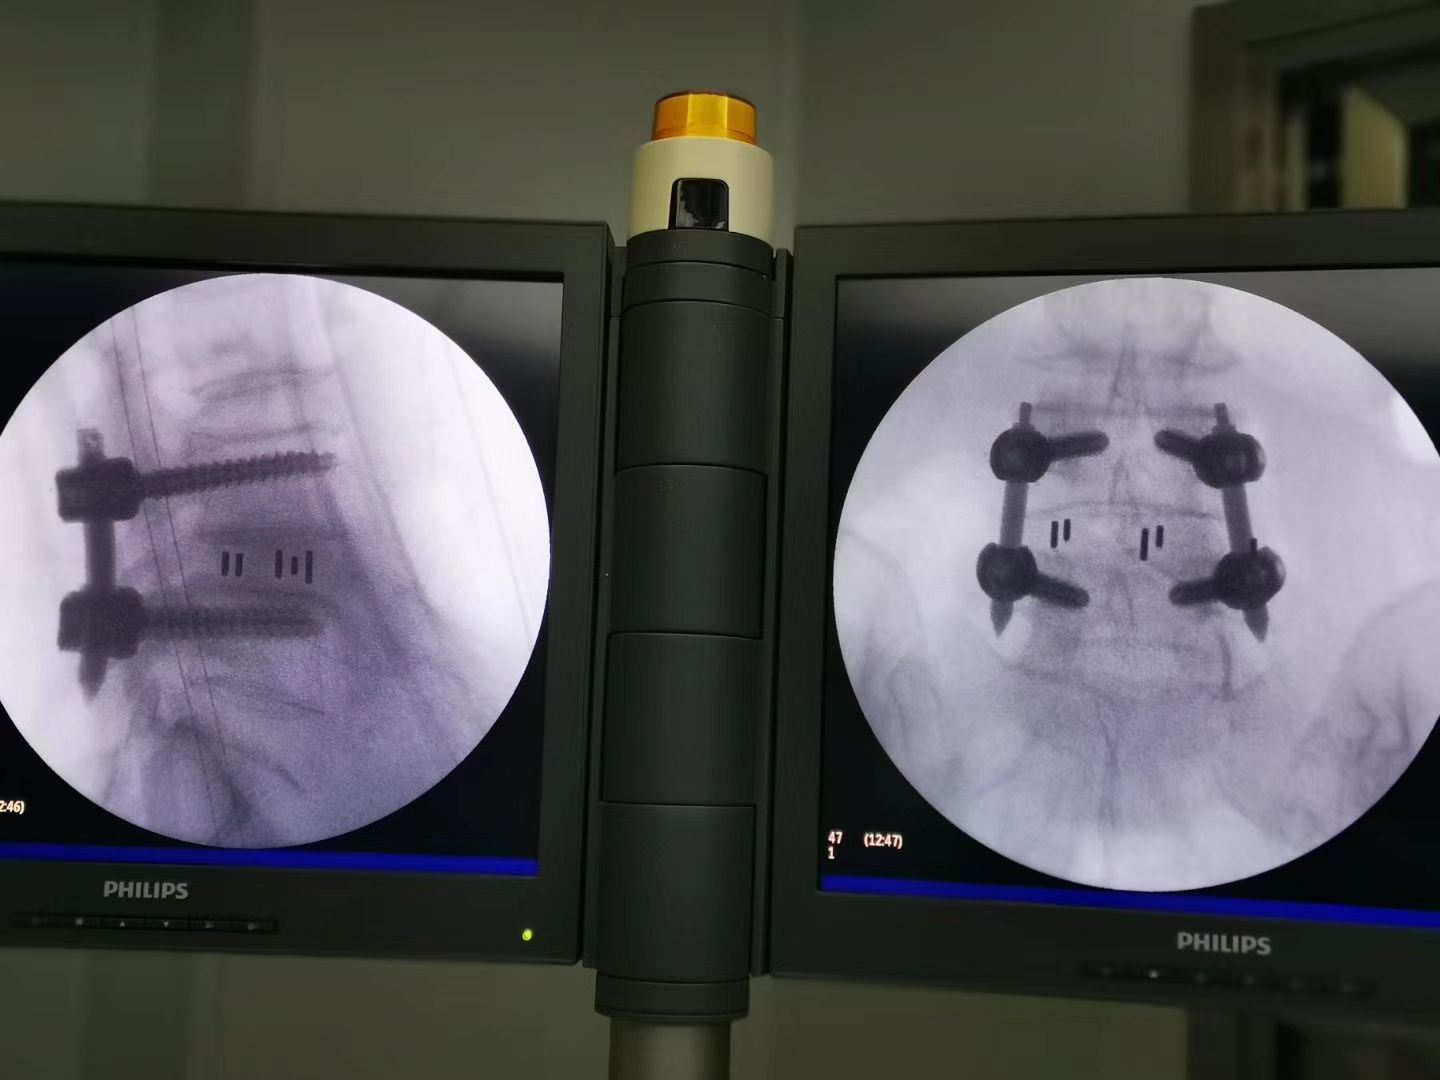

3.輕度的腰椎滑脫(BE-TLIF);

UBE脊柱內(nèi)鏡手術(shù)用全套器械包括:

UBE主鏡,UBE鏡鞘,UBE穿刺器,UBE器械包,UBE融合器械包,UBE大直徑消融電極,UBE動力系統(tǒng),UBE專用融合器,UBE專用cage.

5.對椎管狹窄的同側(cè)減壓及對側(cè)減壓具有其獨特的優(yōu)勢,同時也可行鏡下融合;